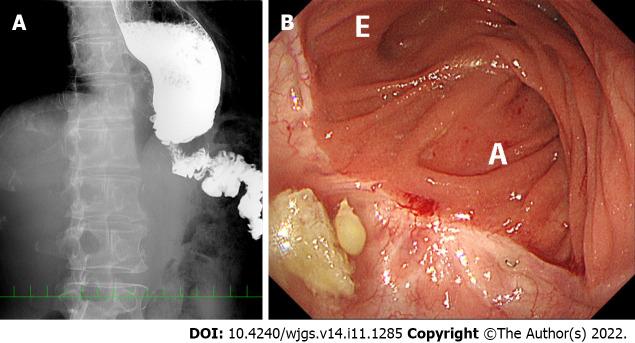

In this paper, we report unusual patients who manifested jejunal limb stricture near the esophageal hiatus without anastomotic stenosis during long-term observation after surgery.

Five patients (2.4%) had unusual jejunal limb stricture after LTG and OEJ, occurring at a mean of 10 mo after initial radical LTG. All five patients had disturbed oral intake and marked weight loss, and two had aspiration pneumonia. Various diagnostic modalities and intraoperative findings in each patient revealed an intact anastomosis, bent or tortuous jejunal limb resulting from loose fibrous adhesions on the left crus at the esophageal hiatus and no cancer recurrence. All five patients were successfully treated by reoperation for adhesiolysis, division of the left crus and rearrangement of the jejunal limb.

CONCLUSION

Disturbed passage through the jejunal limb near the hiatus can occur after some types of OEJ following LTG. We speculate that it may result from a short remnant esophagus, excessive mobilization of the jejunal limb that permits bending or tortuosity and adhesions on the left crus at the hiatus. Prevention for this complication is possible during the original LTG procedure.